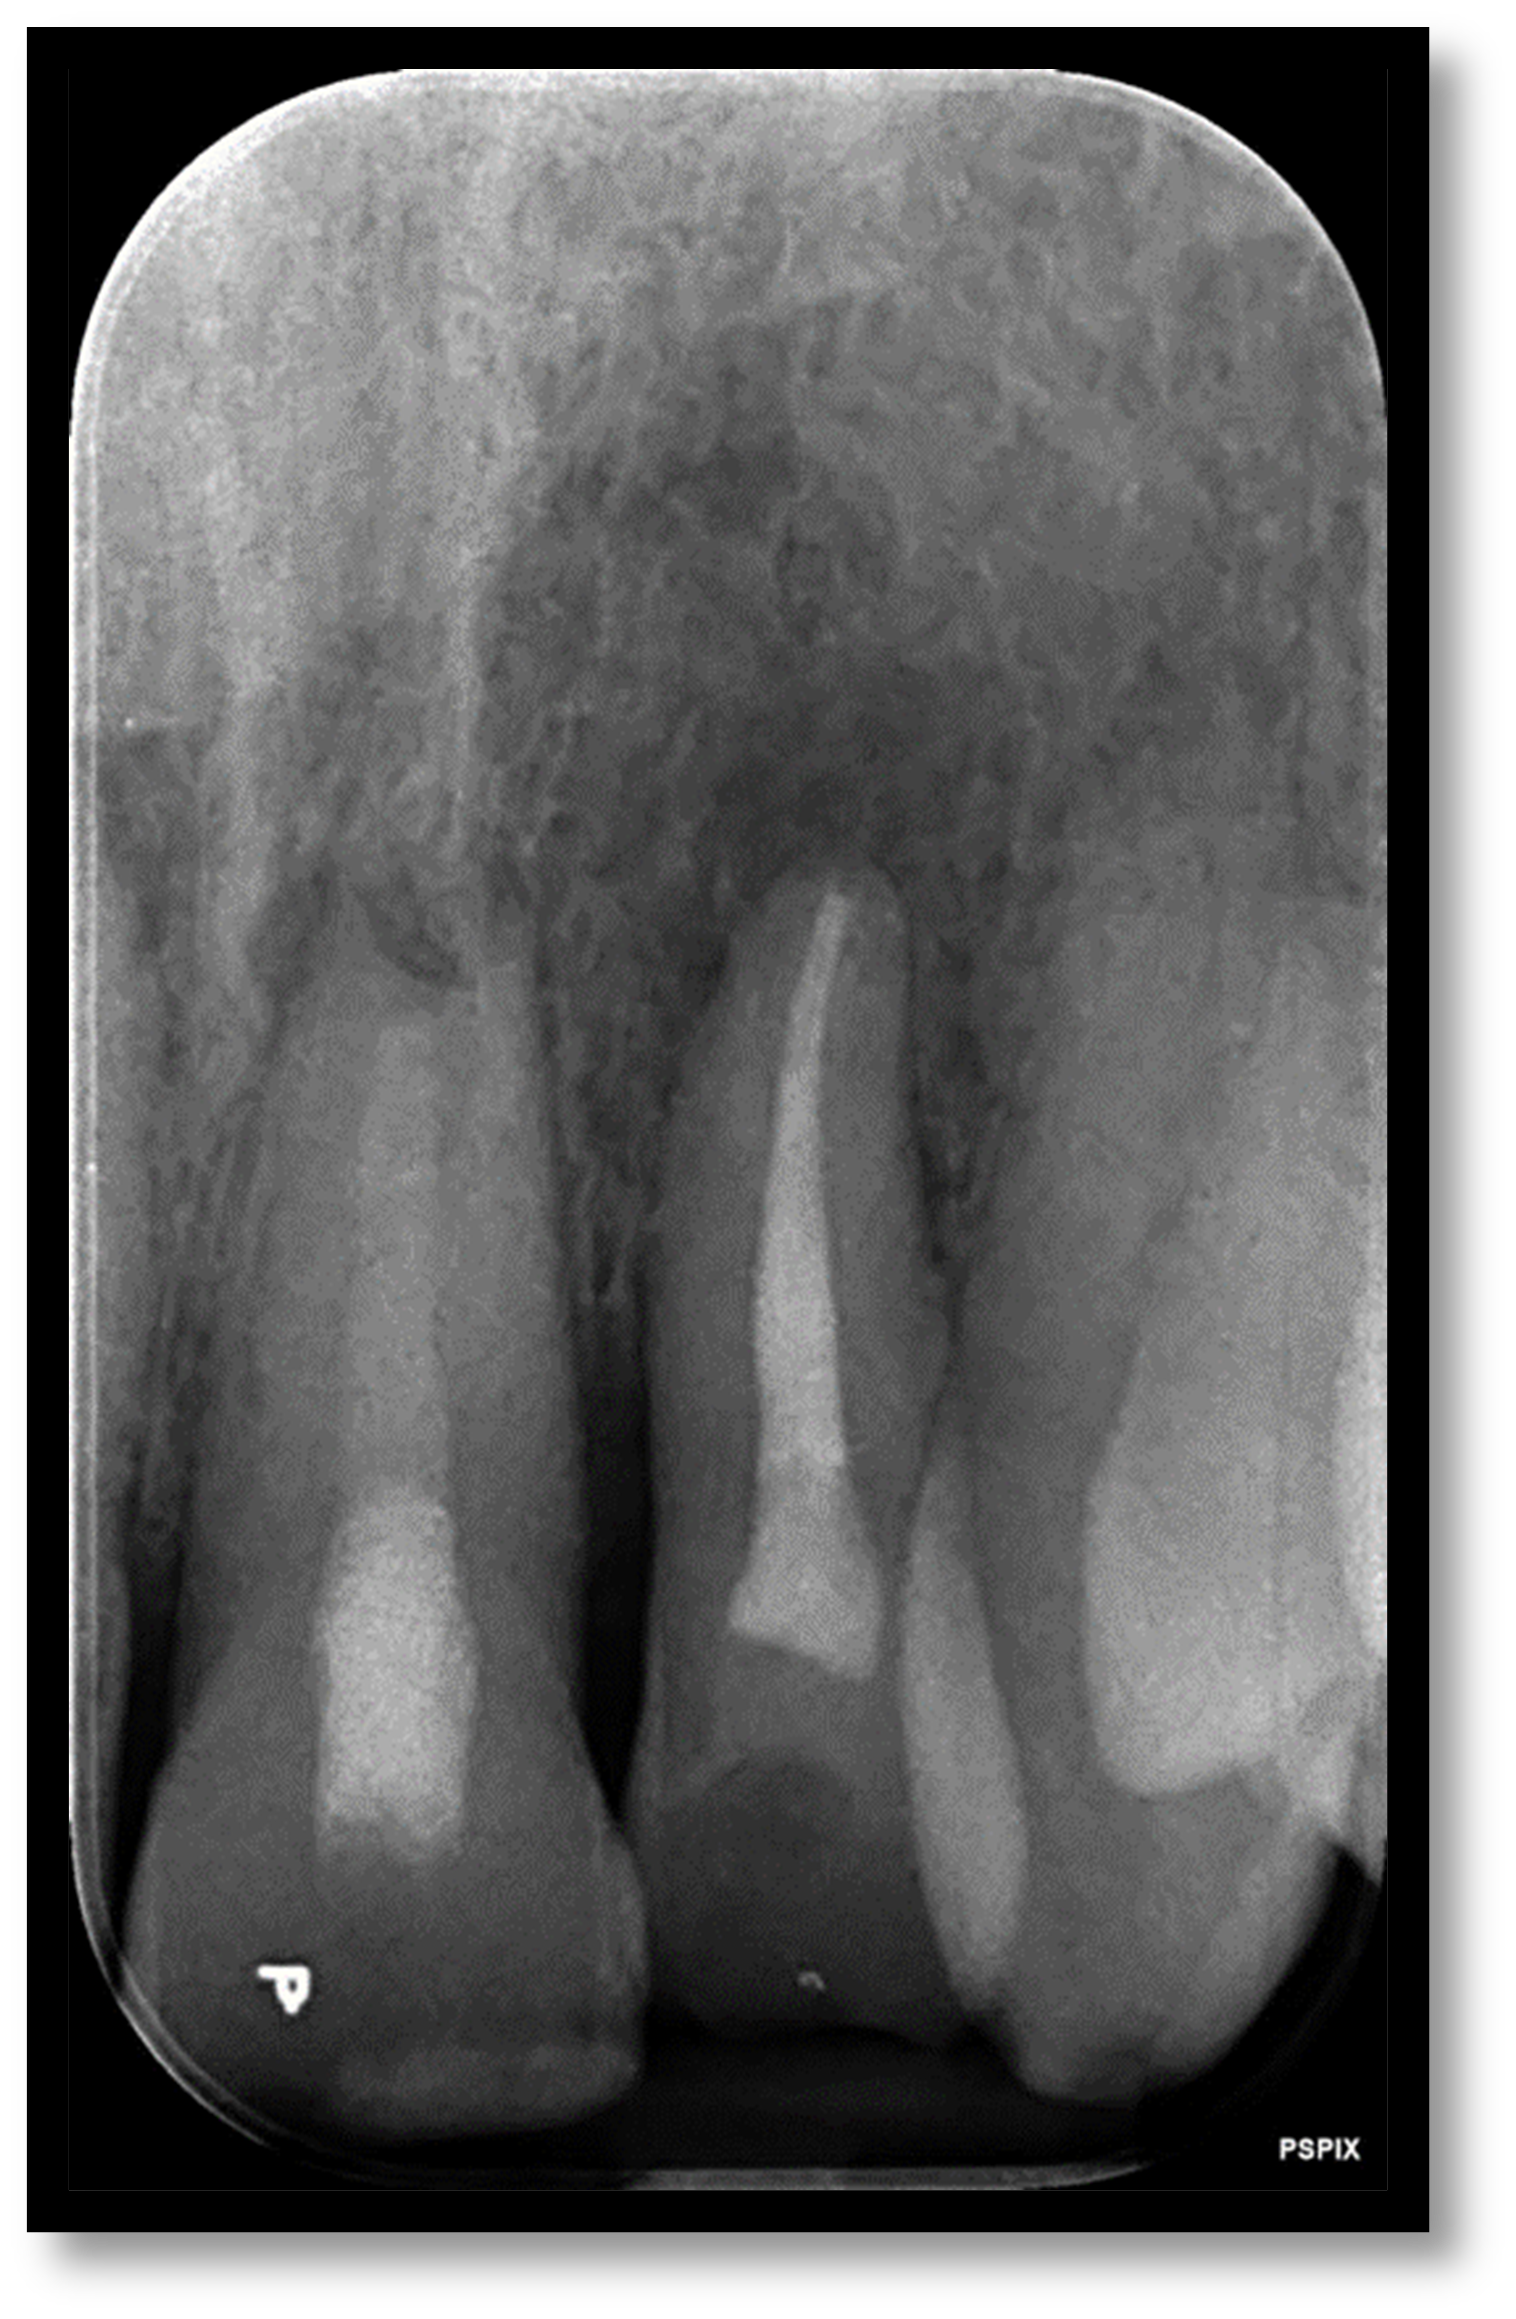

Open/Immature apex management and internal whitening

Pre-op

Procedure Photos